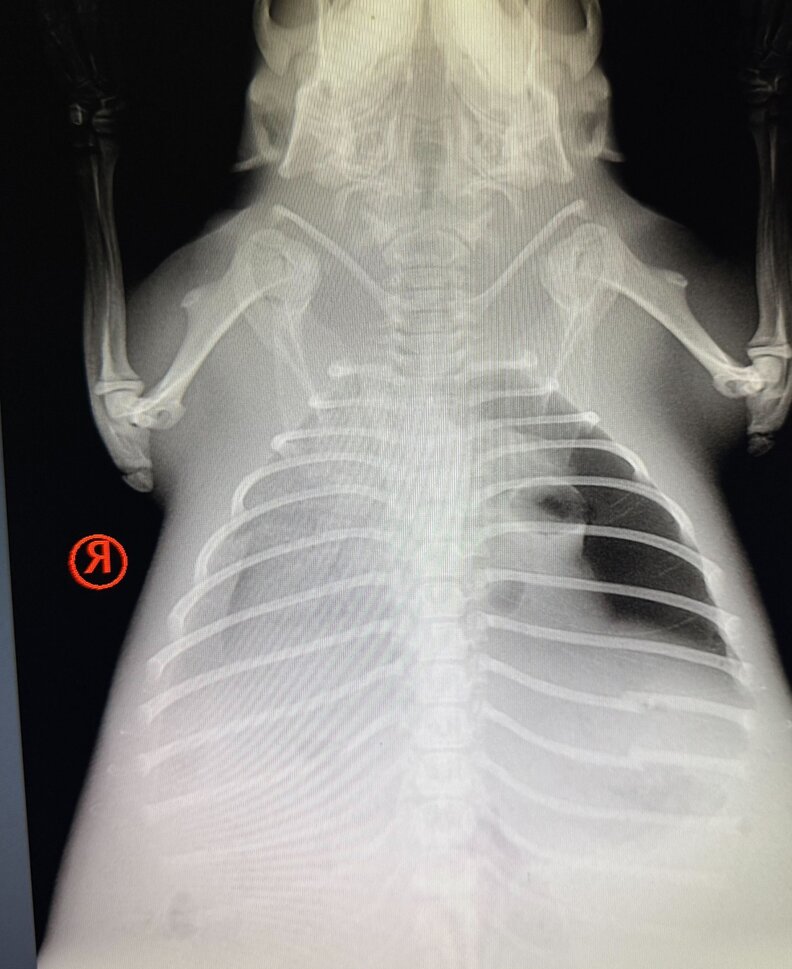

At BRWC, a team of dedicated veterinary staff examined her and uncovered the heartbreaking truth: she was suffering from pneumonia and appeared to have internal trauma, possibly from nearly drowning or from the collapse of her dam.